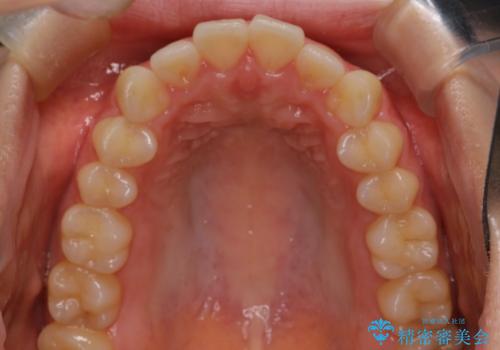

【インビザライン】前歯を下げたい

- 前歯が出ていることを主訴に来院されました。

奥歯を後ろに動かしながらスペースを作ることで、前歯を下げることができ患者さんにも満足していただきました。